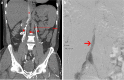

Patients with venous anomalies are at increased risk of developing venous thromboembolism (VTE) and subsequent complications, but they are often under-recognised. While unprovoked VTE may trigger testing for inherited thrombophilias and malignancy screening, anatomic variants are considered less often. Venous anomalies increase the risk due to venous flow disturbance, resulting in hypertension, reduced flow velocity and turbulence. Recognition is important as endovascular or surgical intervention may be appropriate, these patients have a high rate of VTE recurrence if anticoagulation is ceased, and the anomalies can predispose to extensive VTE and severe post-thrombotic syndrome (PTS). In this case series, we present representative cases and radiological images of May-Thurner syndrome (MTS), inferior vena cava (IVC) variants and venous aneurysms, and review the available literature regarding optimal diagnosis and management in each condition.